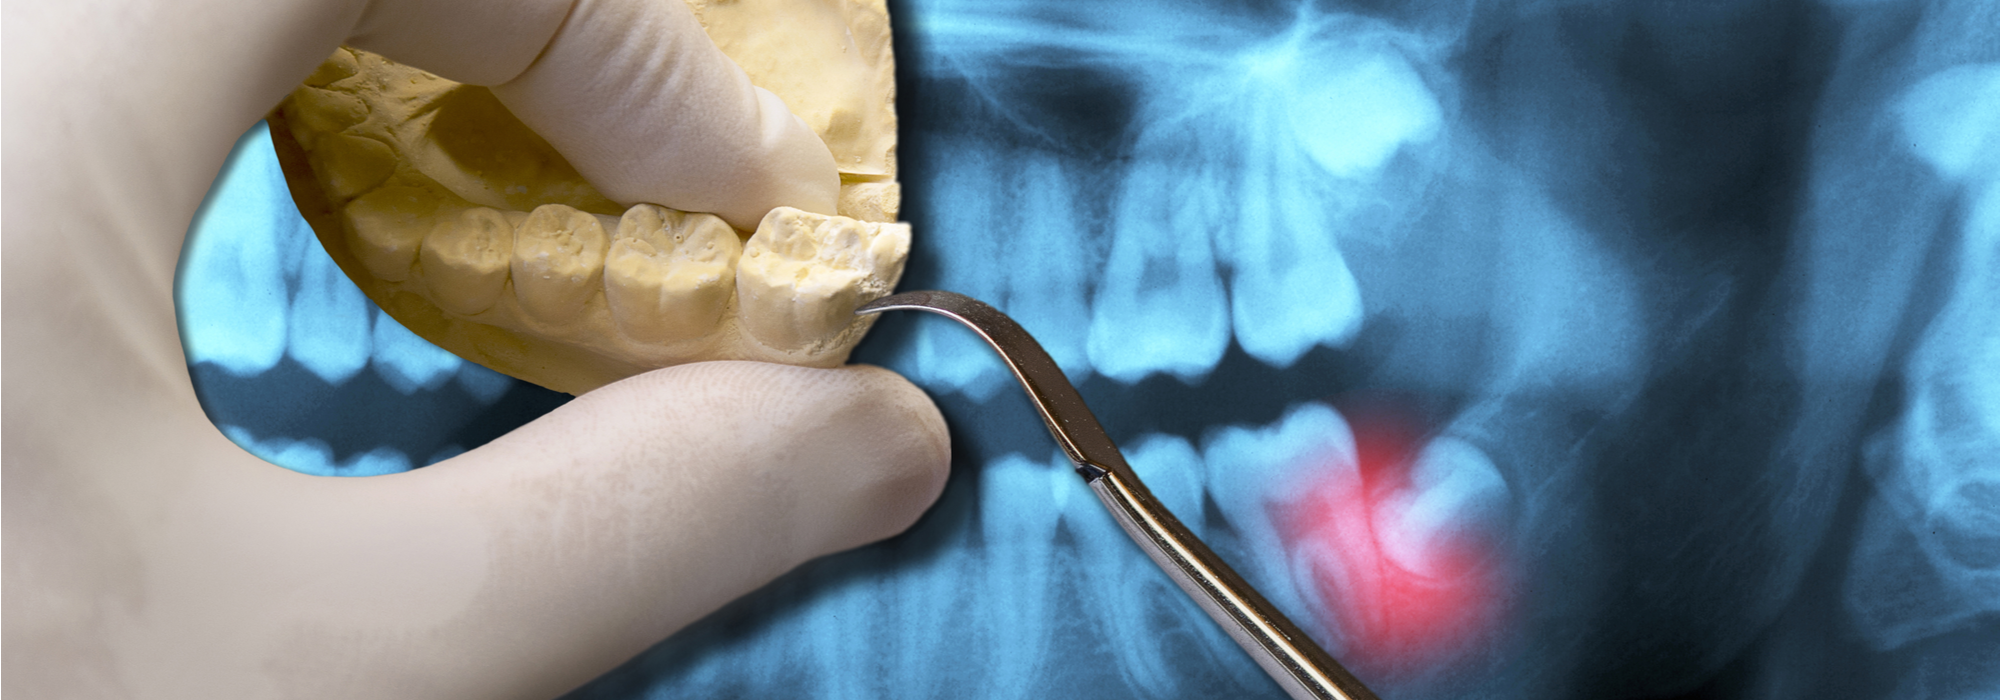

With an oral examination and x-rays of the mouth, Dr. Kunal Rajyan and can evaluate the position of the wisdom teeth and predict if there are present or future potential problems. Studies have shown that early evaluation and treatment result in a superior outcome for the patient. Patients are generally first evaluated in the mid-teenage years by their dentist, orthodontist, or by an oral and maxillofacial surgeon.

WHY SHOULD I HAVE MY WISDOM TEETH REMOVED?

Some of the possible problems related to not removing your wisdom teeth include:

Infection - The most frequent clinical problem we see is pericoronitis, (a localized gum infection). Without enough room for total eruption, the gum tissue around the wisdom tooth can become irritated and infected, resulting in recurrent pain, swelling, and problems with chewing and/or swallowing.

Cyst Formation - Non-infectious diseases may also arise in association with an impacted wisdom tooth. Cysts are fluid-filled “balloons” inside the jaw bone that develop as a result of impacted teeth and slowly expand destroying adjacent jaw bone and occasionally teeth. They can be very difficult to treat if your wisdom teeth are not removed in your teenage years. Although rare, tumors can be associated with the delayed removal of wisdom teeth.

Possible Crowding - Impacted wisdom teeth may contribute to crowding of your teeth. This is most noticeable with the front teeth, primarily the lower front teeth and is most commonly seen after a patient has had braces. There are a number of factors that cause teeth to crowd after braces or in early adulthood. Retained, impacted wisdom teeth may be a contributing factor. Unless you have an active problem when you see the oral surgeon, the reason for removal is primarily to prevent long-term damage to your teeth, gums and jaw bone.